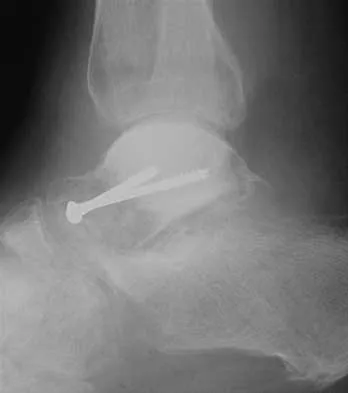

A 32-year-old man sustained a closed injury after falling 25 feet from a roof. His ankle and foot are severely swollen. Radiographs and CT scans are shown in Figures 29a through 29d. Initial management should consist of